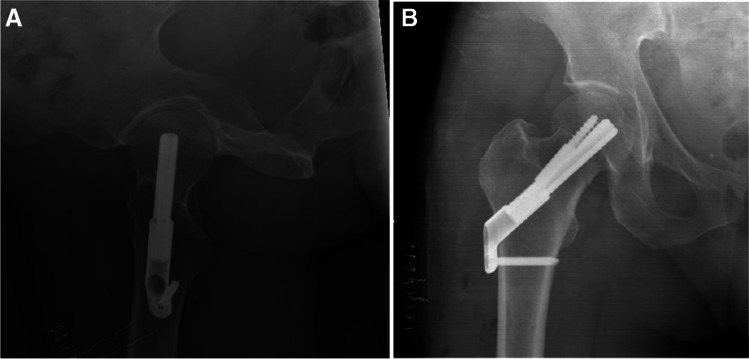

Fig. 5.

A, B AP and lateral radiographs post-operative day 1, demonstrating fixation of the fracture with FNS

Fig. 6.

A, B AP and lateral radiographs from last follow-up 27 months after surgical treatment. Returned to her preinjury mobility status